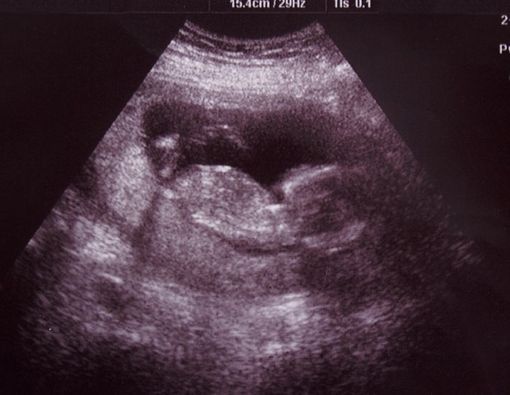

Missed abortion juga rentan terjadi pada awal kehamilan, tepatnya 20 minggu. Kondisi ini tidak bisa dideteksi tanpa pemeriksaan USG.

Biasanya, dokter melakukan diagnosis untuk missed abortion ketika tidak dapat mendeteksi detak jantung bayi pada pemeriksaan kandungan. Karena itu, penting untuk rutin mengecek kondisi kehamilan.